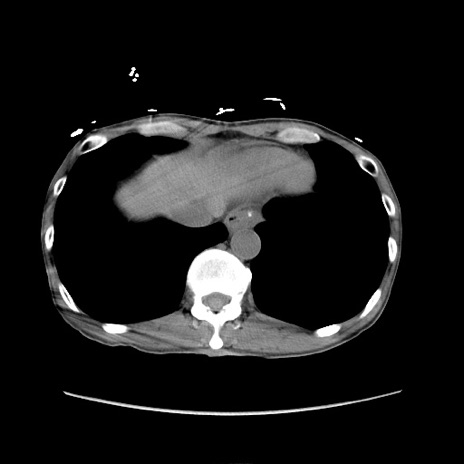

冠状断像

症例11(横断像)

【症例】 60歳代男性

【主訴】 下腹部痛

【現病歴】 本日夜中より下腹部痛の症状認め、受診。

【既往歴】 膀胱癌(膀胱全摘+尿管皮膚瘻術) 、胃癌術後

【身体所見】 BT 35.3℃、PR 58/min、BP 136/98mHg、腹部平坦、軟、腸蠕動音±、ストマ留置あり、左上腹部~正中部に圧痛あり、反跳痛なし。

【データ】WBC 5100、CRP0.01